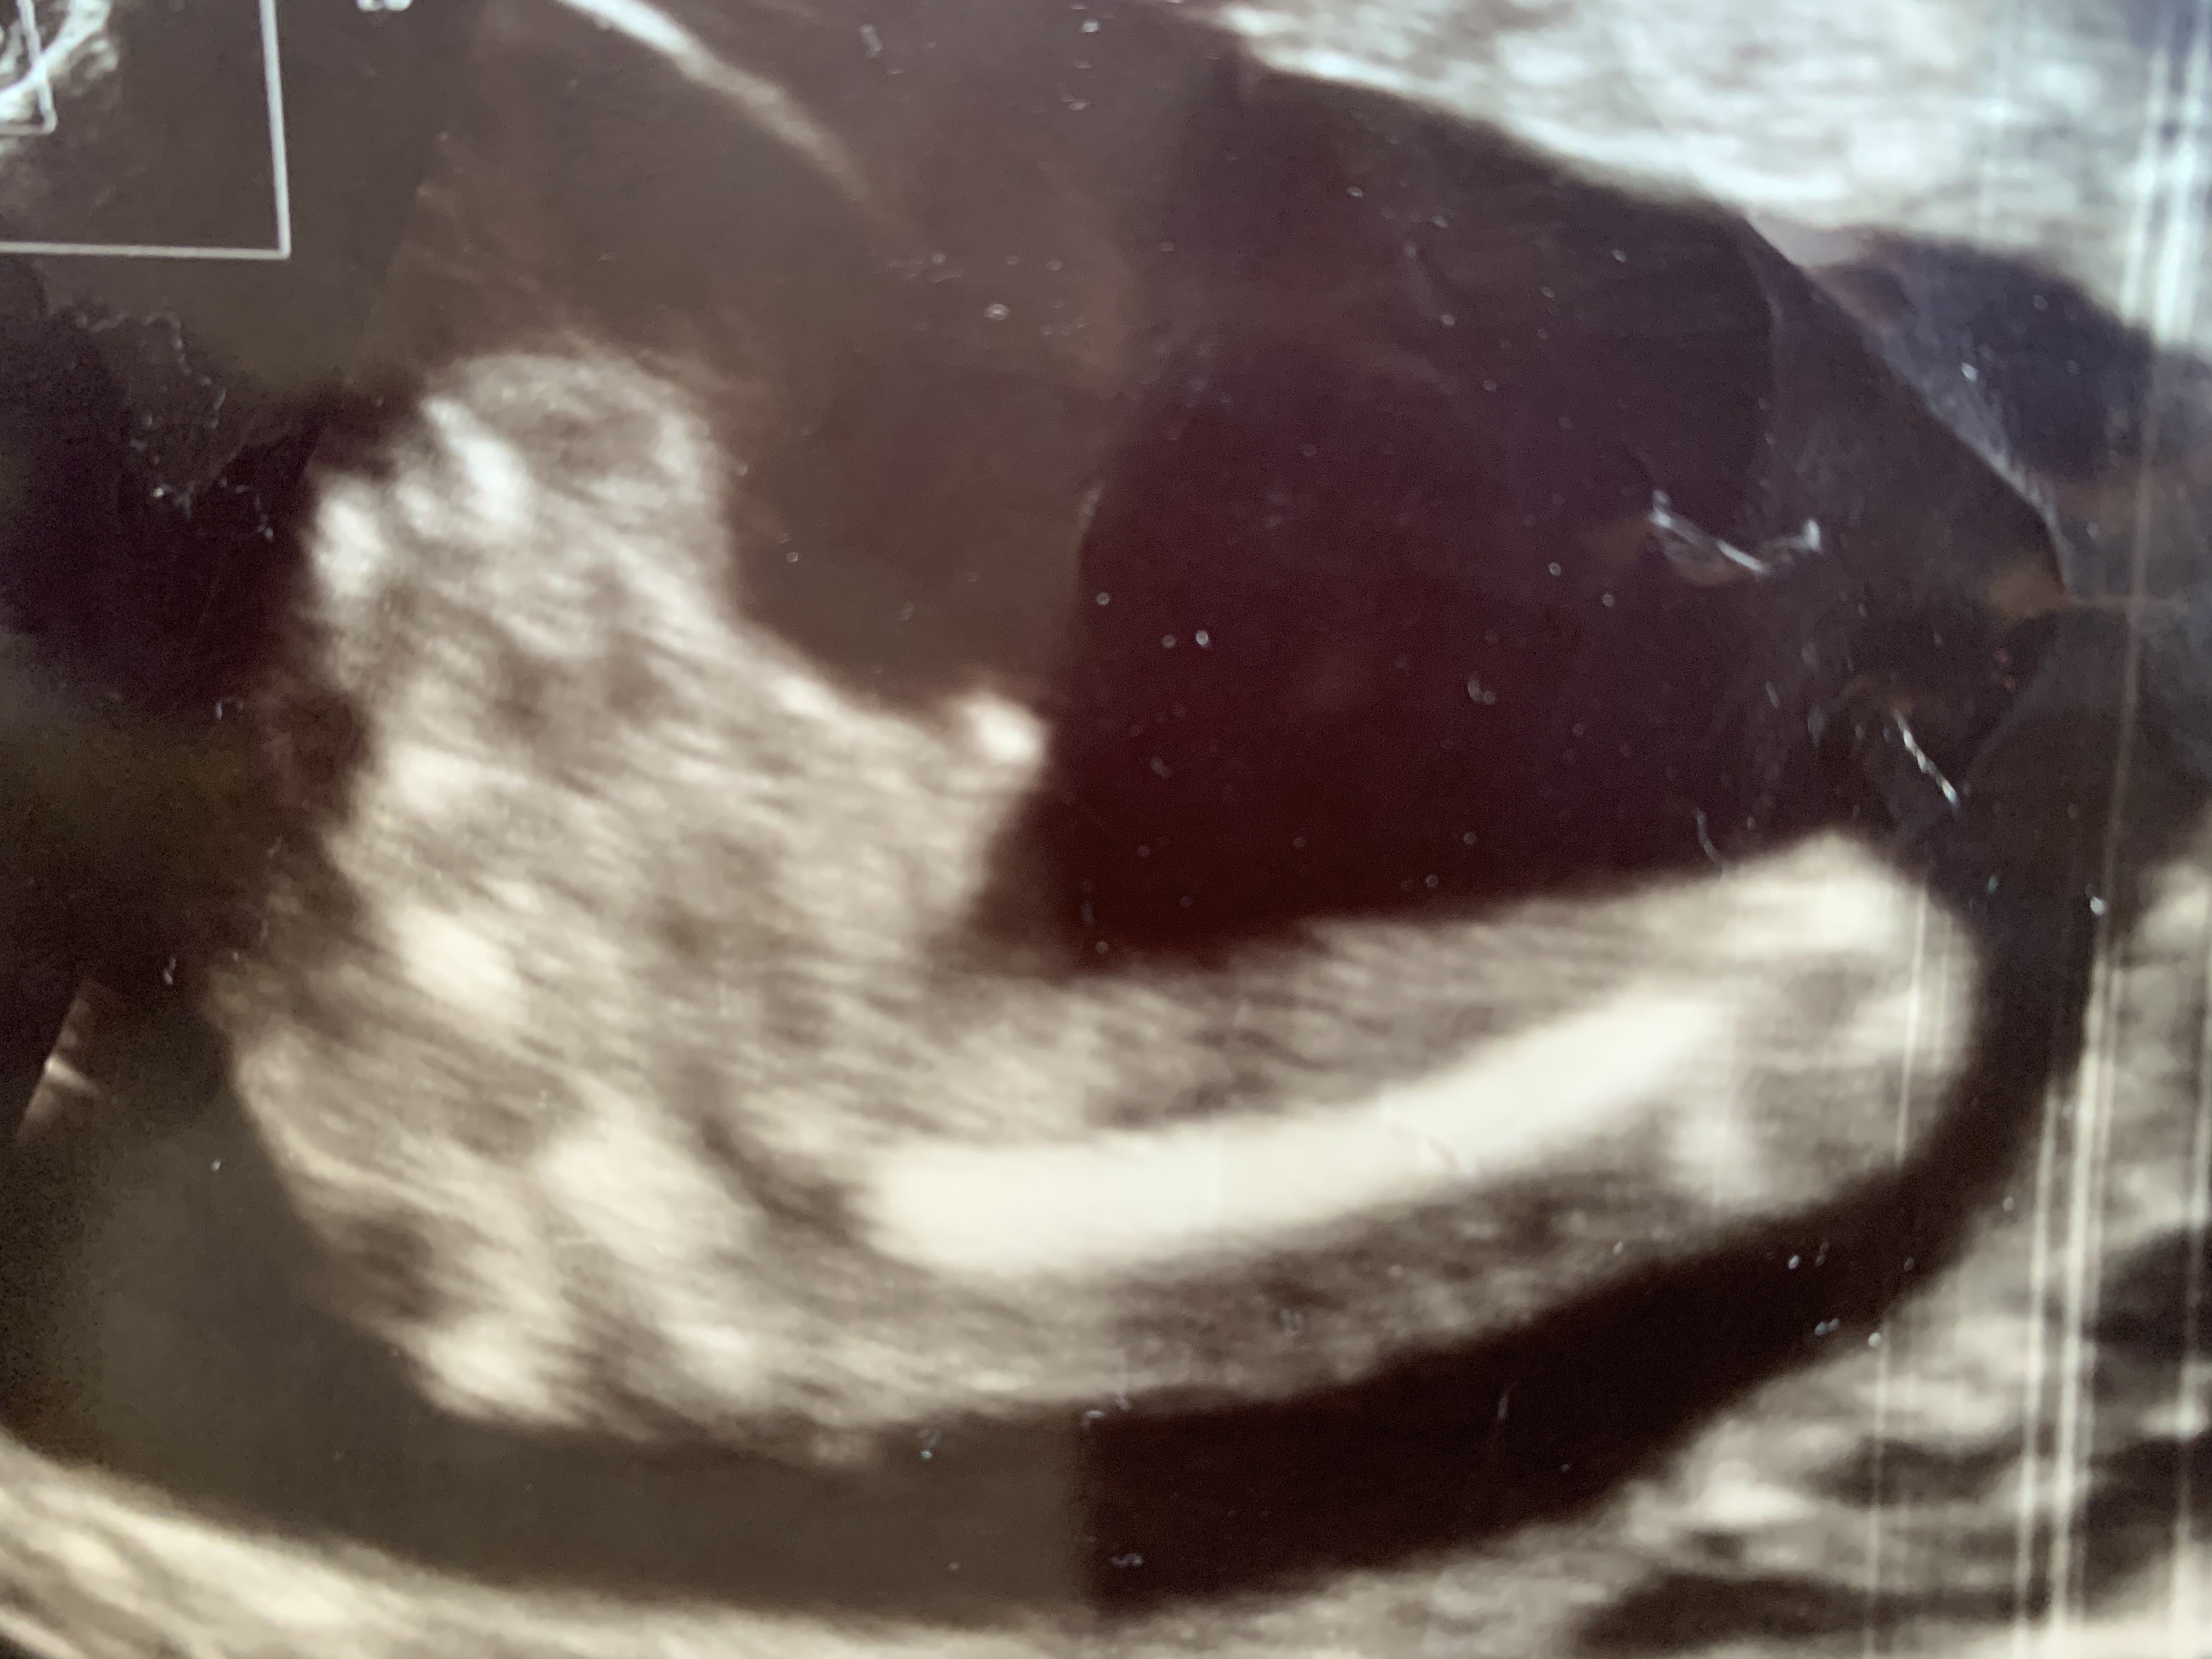

Witam w 19 tygodniu ciąży dowiedziałam się ze będę miała dziewczynkę w 20 tyg okazało się jednak , że to chłopak. Sama już nie wiem bo na jednym usg widać na pewno dziewuche a na drugim chłopca. Może to pempowina ?? Może ktoś mi pomoże rozwiązać ta zagadkę

• 4A8F5FF1-76CA-4DE0-AC12-5EDF08E820F2.jpg

4A8F5FF1-76CA-4DE0-AC12-5EDF08E820F2.jpg

596,4 KB · Wyświetleń: 44 114

596,4 KB · Wyświetleń: 23 768